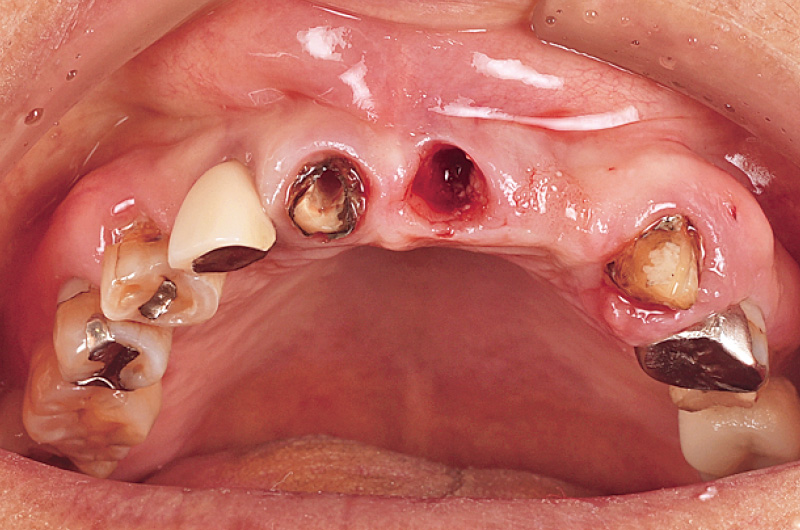

80歳の女性の患者で、主訴は前歯にインプラントを入れて欲しい、とのことで来院された。21は自然排膿を生じながらも強い痛みがないため長年放置していたが、腫脹や疼痛を繰り返すようになったため、治療介入することとした。

エンドペリオ病変を併発しており、抜歯適応と判断した。11, 12は、太くて長いダウエルコアが装着されていた。12の根尖部に13の埋伏歯を認め、それにより12の歯根が吸収している。保存の可否を判断するために、ロングスパンブリッジを撤去しようとしたこところ、容易に撤去でき、21に関しては歯根ごと抜去された。11, 12は残存歯質が乏しく歯肉縁下だったため、保存不可と判断した。患者の強い希望もあり、インプラントによる補綴設計を計画した(図2)。

最終的な補綴設計は、11, 21にインプラントを埋入し、12, 22への遠心カンチレバーとすることとした。21, 22どちらも骨欠損が大きいが、根尖側にインプラントの初期固定が取れるであろう21への埋入とした。治療順序としては、21, 22に骨造成をまず行い、6か月の治癒期間を経たのちにインプラント埋入を行うこととした。